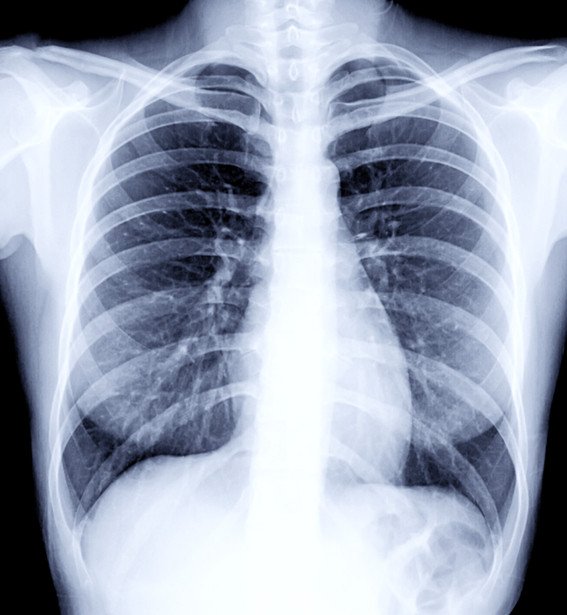

Digital Xray

The next development in x-ray technology is digital x-rays. They provide the same ease of use and comfort as conventional x-rays for finding anomalies in bones, teeth, organs, and other body components. However, they are more efficient than traditional x-rays.